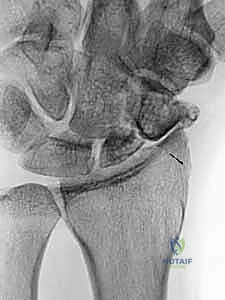

5. تحضير العظم الزورقي (Debridement)

يتم فتح كبسولة مفصل الرسغ للوصول إلى العظم الزورقي المكسور. يقوم الدكتور هطيف بتنظيف منطقة عدم الالتحام بالكامل، وإزالة كل الأنسجة الليفية، والتكيسات، والعظام الميتة (النخرية) باستخدام أدوات دقيقة (Curettes) ومثاقب صغيرة، حتى يصل إلى حواف عظمية صحية تنزف دماً (علامة على الحيوية). هذا يترك فجوة بحاجة إلى الحشو.

![تحضير وتجهيز العظم الزورقي لاستقبال الطعم](/media/hutaif_opertive/hutaif-ch